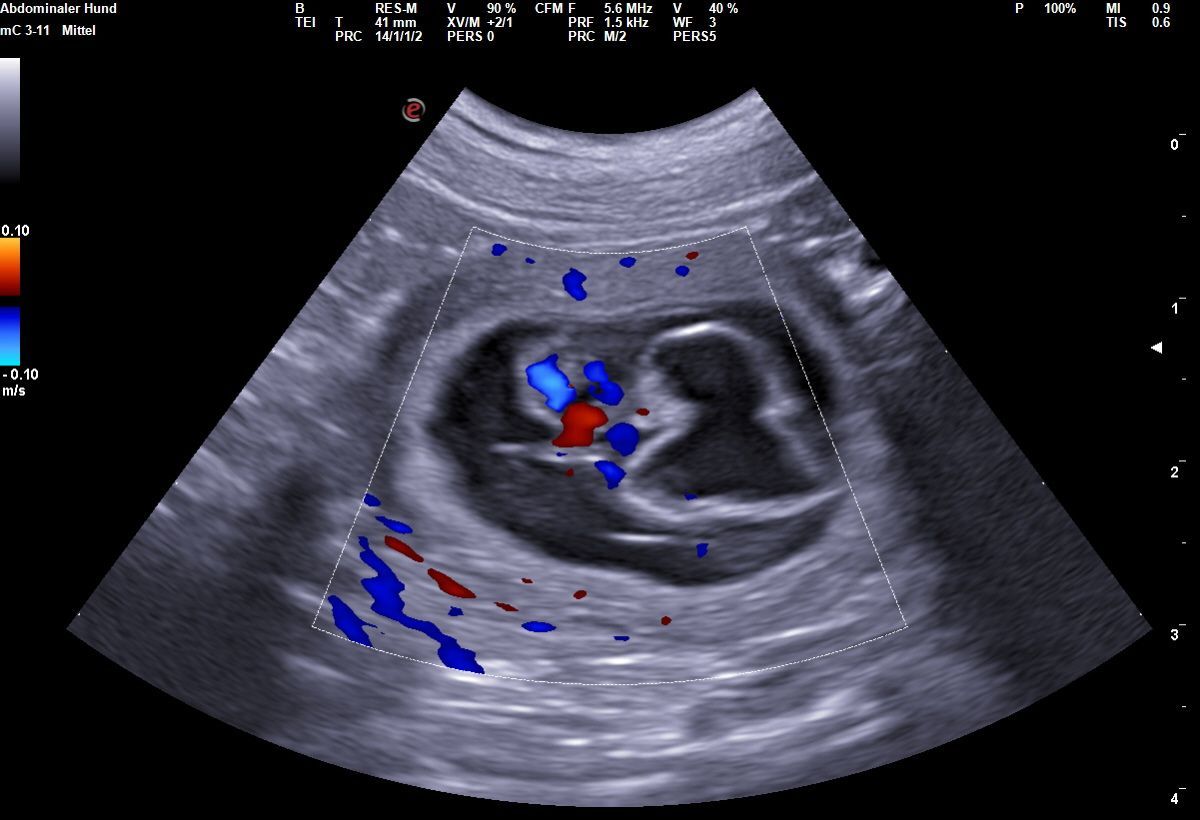

| 26 | "24-28. Tag Dies ist der beste Zeitpunkt, um die Trächtigkeit anhand des Herzschlags zu diagnostizieren. | |||

| 27 | Die Embroynen sind etwas walnussgroß und sind gleichmäßig im Uterus verteilt." | |||

| 28 | 16,6 | Ultraschall Trächtigkeit bestätigt | ||